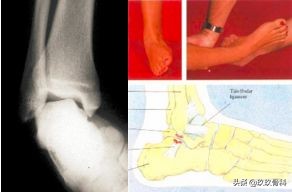

抽屉试验

术中抽屉试验

内翻应力试验

辅助检查

- X线 踝关节正侧位(必要时应加照踝穴位)

- B超

- MRI

应力位片